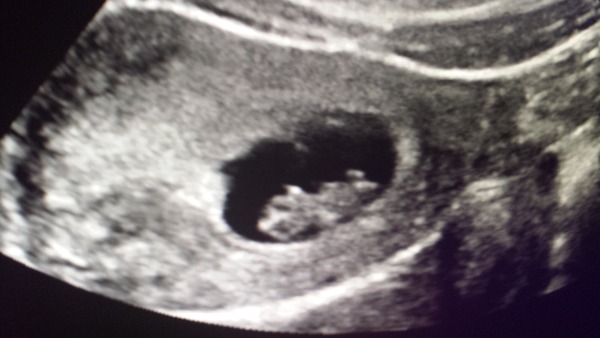

Firstgo 8+1 today. Scanned myself today. Growing beautifully and lovely heartbeat!

Lovely scan pictures Lauren, Bunch and First! It's amazing to see the different stages!

Lovely scan pic First!

Aww, First that's a lovely photo.

Lovely scans bunch and first!

First what a cute little bean.